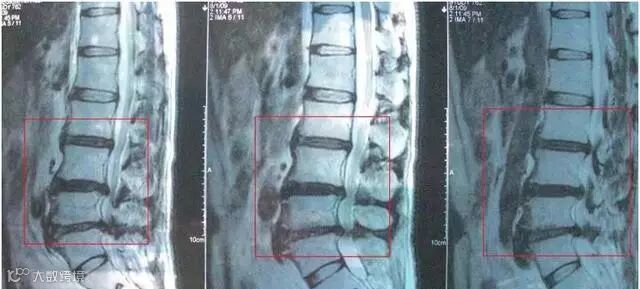

医院花了400多照核磁共振

医生说腰椎间盘突出已经很严重了

我们怀孕时后纵韧带松弛

椎间盘容易膨出

加上体重增加

腰背痛发生率明显比一般人高

另外长期睡不合适的床,久坐、受寒等

也会让我们的腰椎颈椎变形

所以腰肌劳损、腰间盘突出、

腰椎增生、错位等多种腰椎病

成了现代人的通病